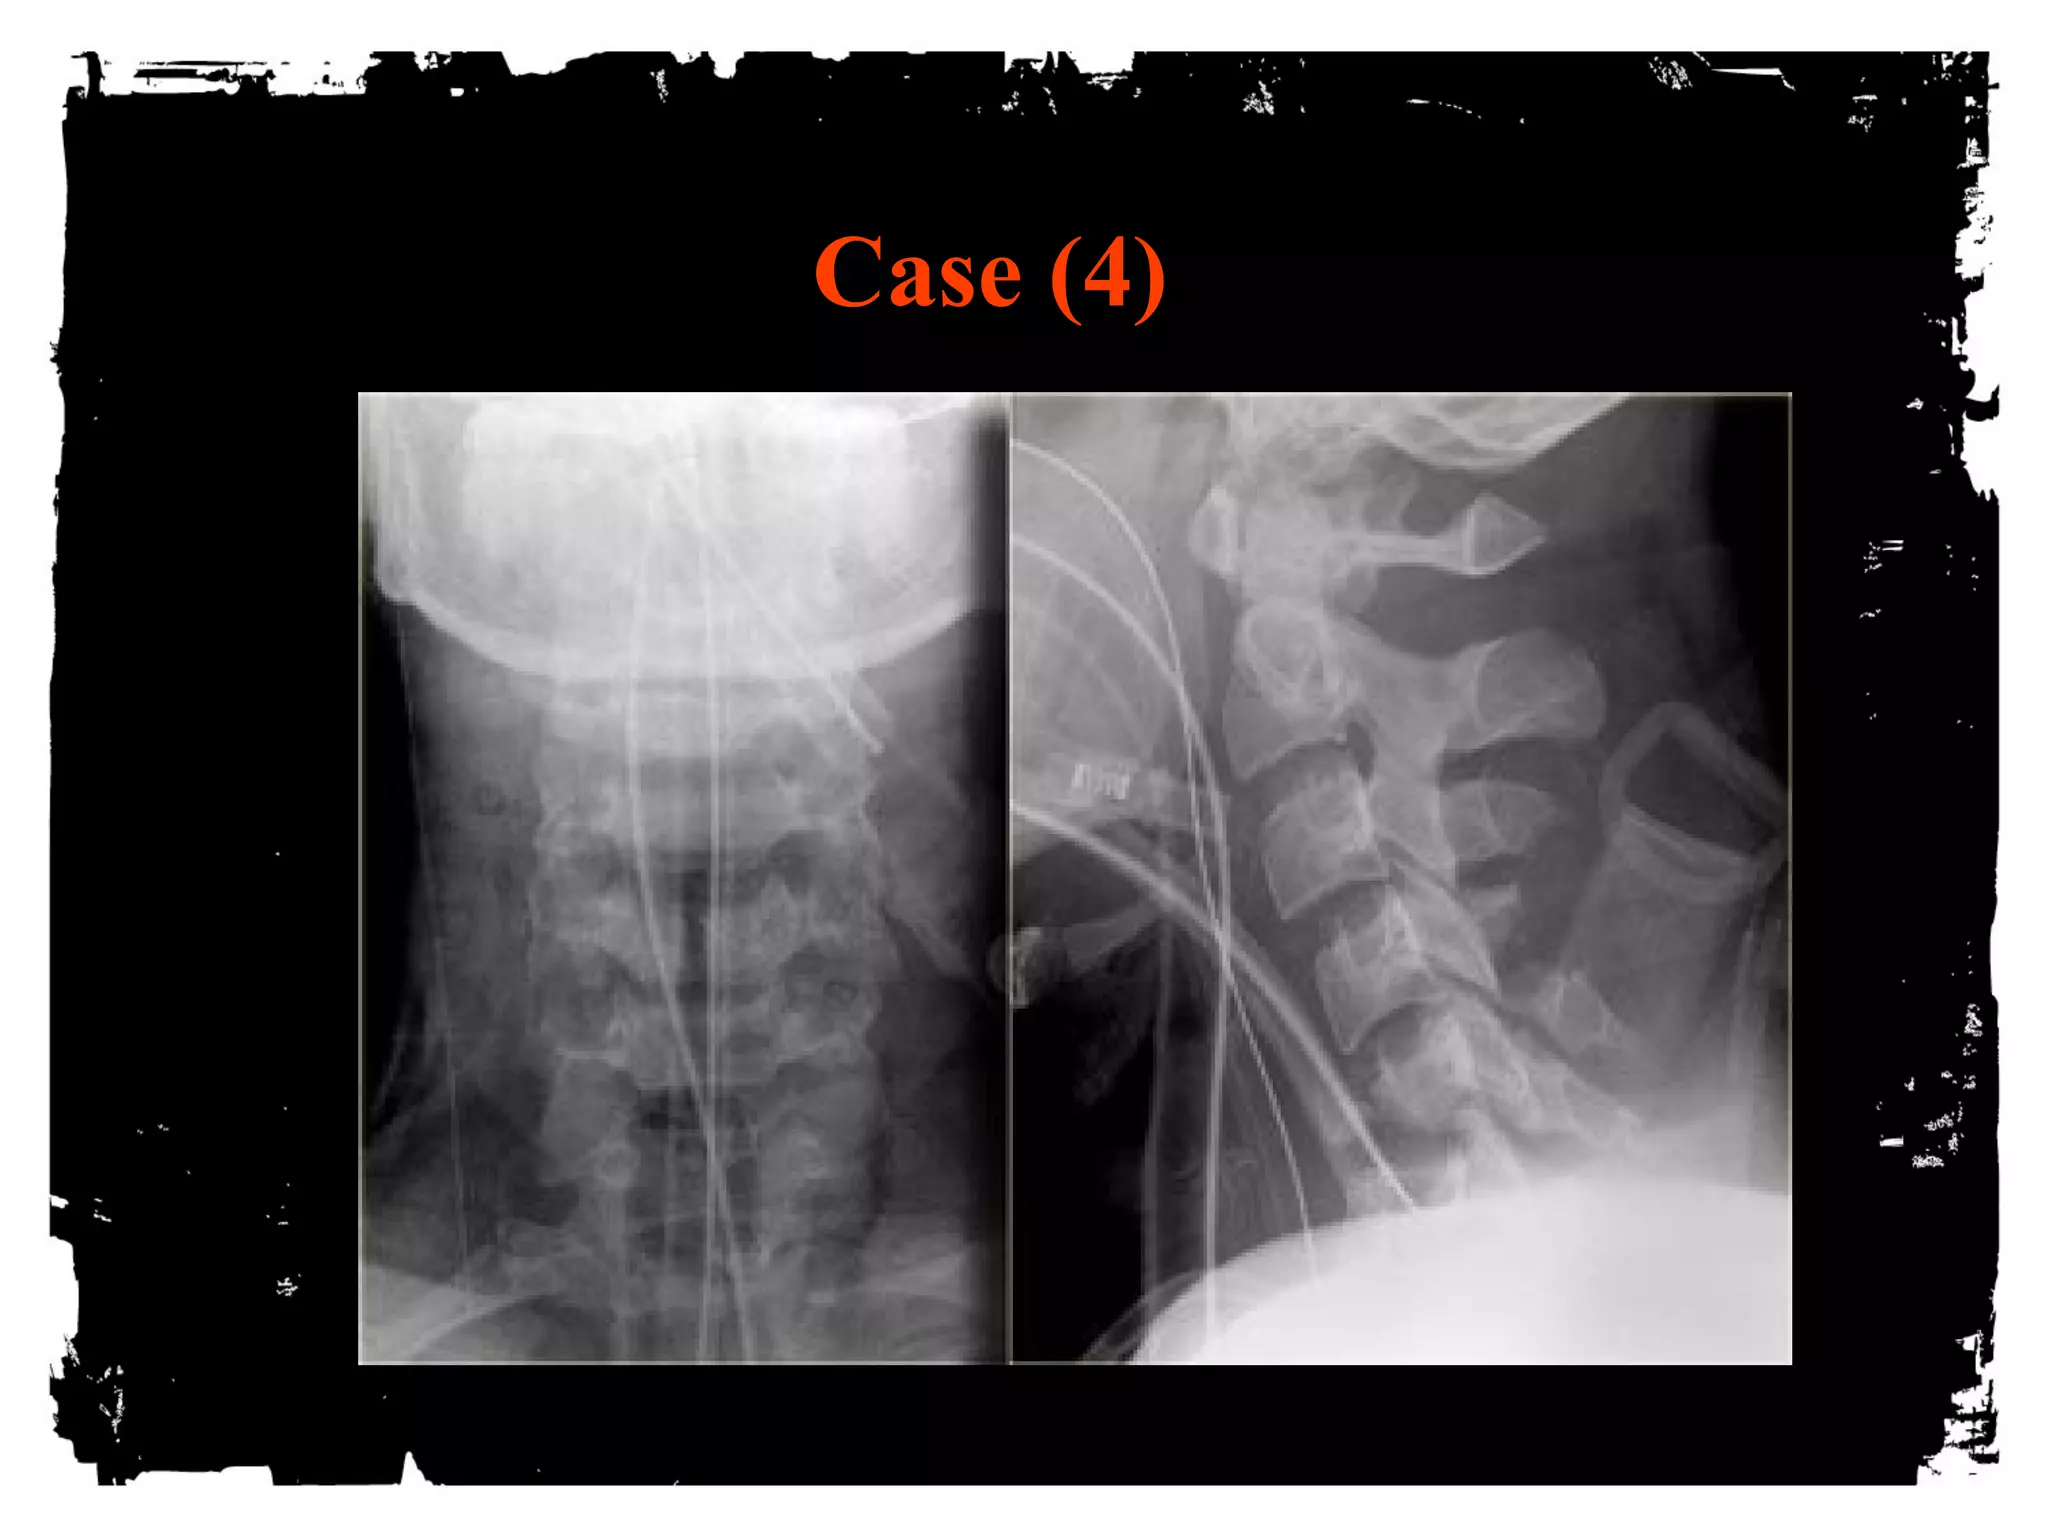

Case (4)

Flexion Tear Drop

Flexion+compression (MVA)

Teardrop fragment comes from the anteroinferior

aspect of the vertebral body

Larger posterior part displaced backward into the

spinal canal

Facets joints and interspinous distances usually

widened, disk space may be narrowed

70% of patients with neurologic injuries

Unstable fracture (complete disruption of ligaments

and anterior cord syndrome

Flexion Tear Drop Flexion+compression (MVA) Teardrop fragment comes from the anteroinferior aspect of the vertebral body Larger posterior part displaced backward into the spinal canal Facets joints and interspinous distances usually widened, disk space may be narrowed 70% of patients with neurologic injuries Unstable fracture (complete disruption of ligaments and anterior cord syndrome

• 112.